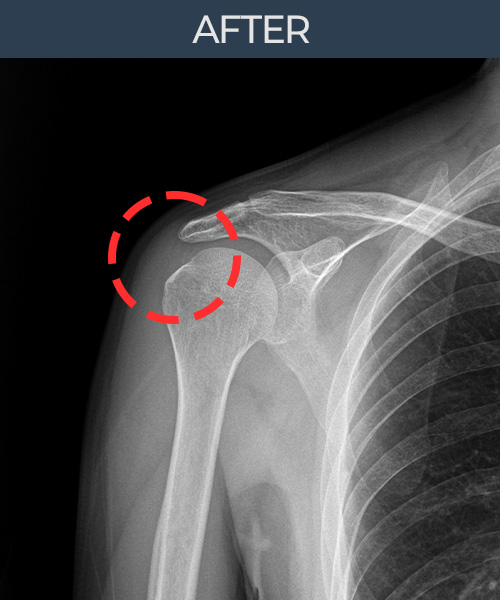

수천건의 수술 경험을 바탕으로 정확히 진단하여

인대파열을 비수술로 치료합니다.

플래티넘정형외과에서는 수술이 필요없는 인대파열만을

정확히 진단하여 특허받은 술기로 비수술로 치료합니다.